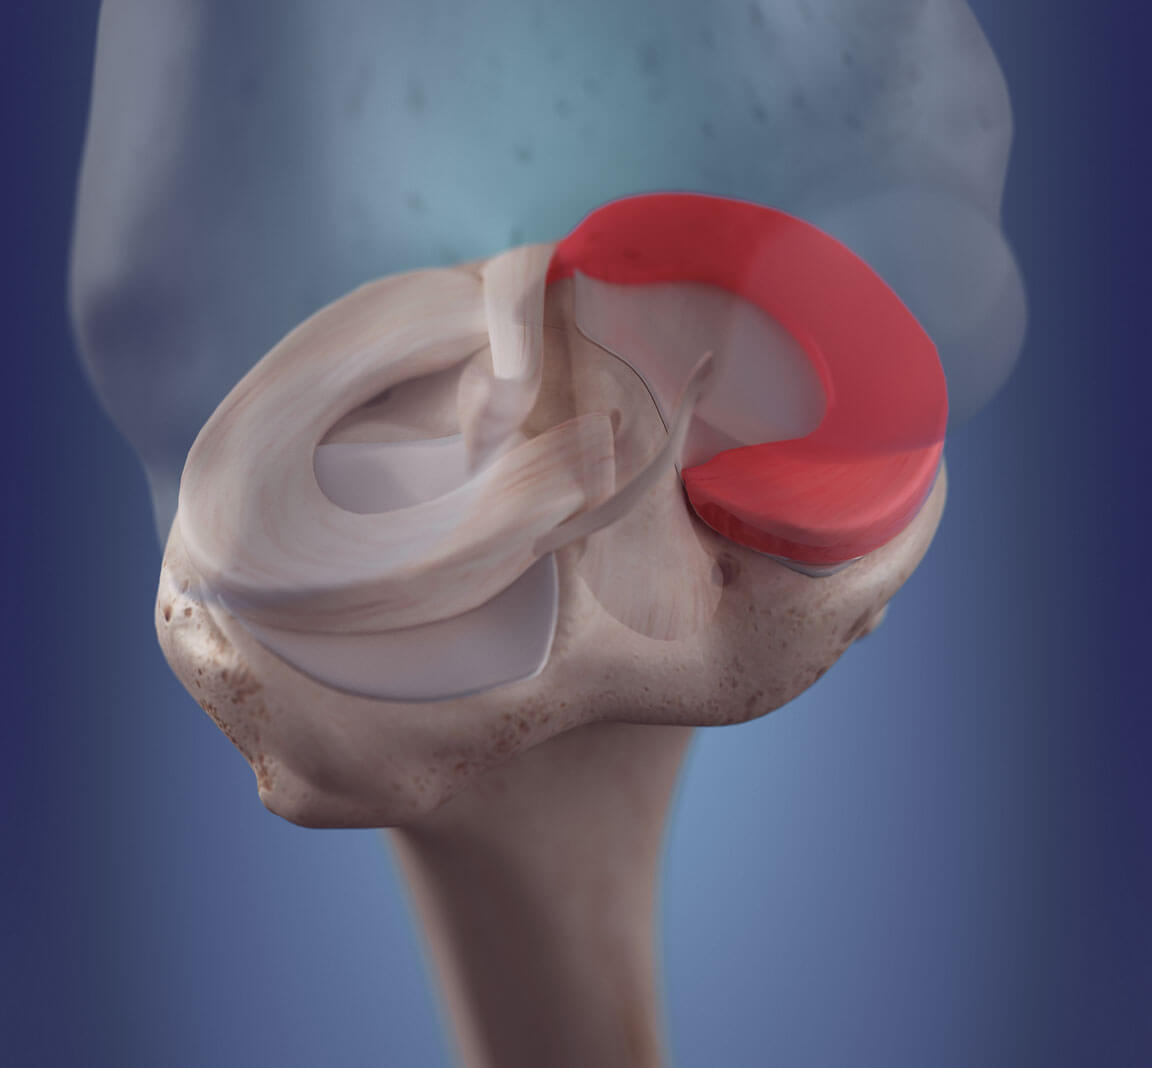

There are two menisci in each knee – one on the inner side of the knee (medial menisci) and the outer side of the knee (lateral menisci). The meniscus is a C-shaped piece of thick and fibrous cartilage that is responsible for providing shock absorption and cushion to your knee.

The meniscus also keeps the knee steady by distributing your weight equally across the knee bones. Its wedge-shaped structure also further keeps the knee joint stable.